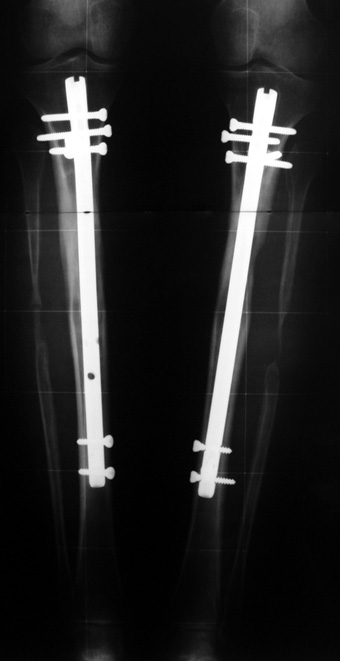

The application of the external fixator: Three Schanz screws are placed distally and three screws are placed proximally. At least 1 mm of distance shall remain between the screws and the nail.

In selected cases, we prefer to use a combination of a unilateral dynamic axial fixator and an interlocked intramedullary nail, in order to protect the length and alignment after the completion of the lengthening procedure. As a prerequisite for this technique, the narowest diameter of the medullary cavity shall be wider than 7 mm and the length of the nail segment distal to the osteotomy site shall be at least 8 cm. after the completion of the lengthening procedure.The intramedullary nail neutralizes shear and bending forces on femur during lengthening, shortens external fixation time, and protects newly formed bone against fractures. In our series, subtrochanteric osteotomy was performed in one case. No varus angulation occured despite the intramedullary nail.

Ilizarov stressed the significance of endosteal blood circulation for distraction osteogenesis. Although we placed the intramedullary nail after reaming the femur in all cases, the time for callus formation was not longer than expected. Thus we found that there is no slowing in the rate of new bone formation due to disruption of medullary blood flow. The rationale of this finding is revascularization that occurs following reaming of the medullary cavity, the fixation stability with the intramedullary nail and early functional weight bearing. The potential disadvantages of a combined use of external and internal fixation metods are increased blood loss, intramedullary infection, risk of fat embolism and excessive metal load.The most fearsome complication is a deep intramedullary infection (panosteomyelitis) triggered by pin tract infection.No such complication was encountered in our series. In order to avoid this complication, after the completion of lengthening the nail shaill be interlocked from the medial side, and contact of internal and external fixator pins shall be avoided.